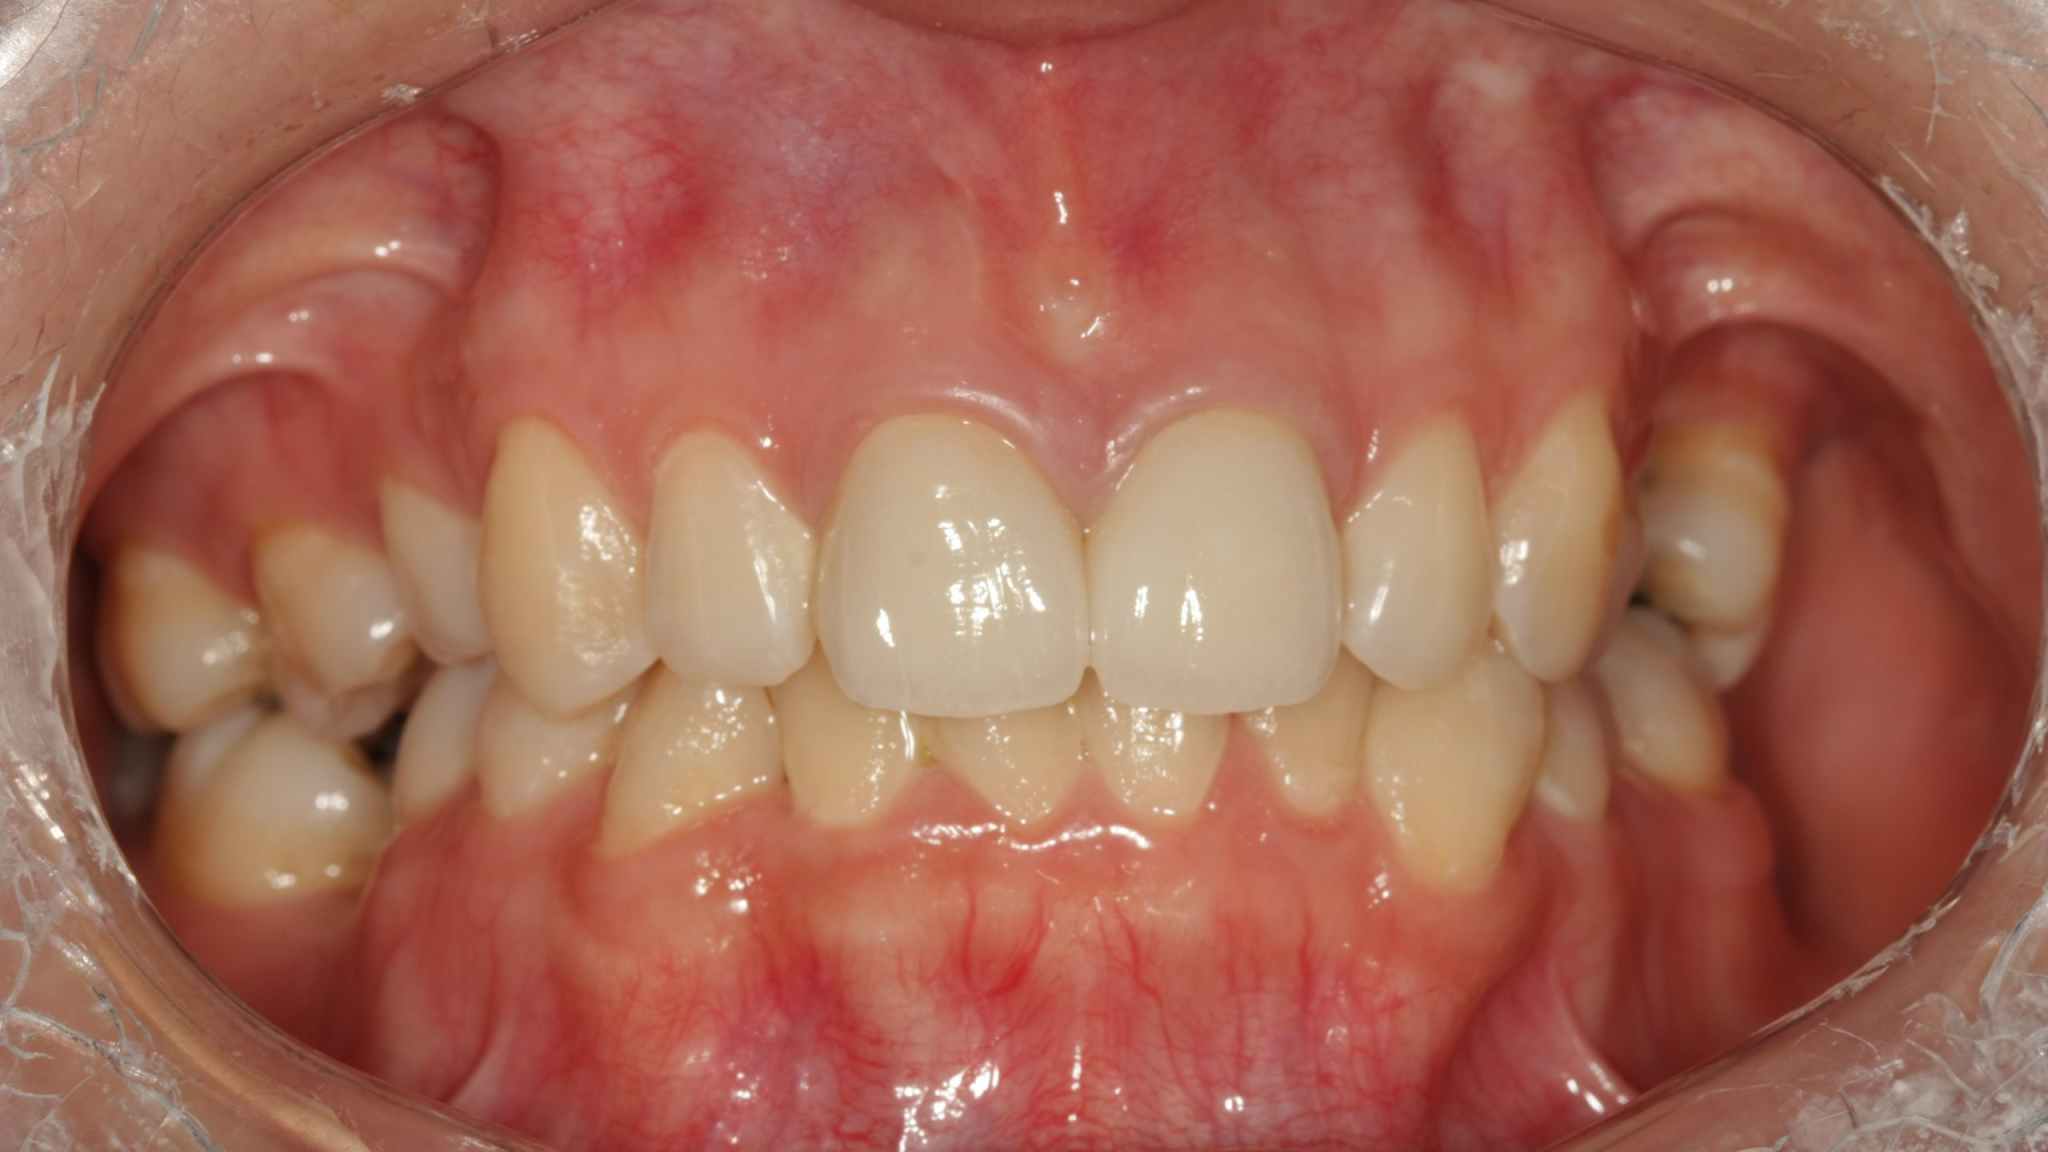

Preoperative photo

Postoperative photo